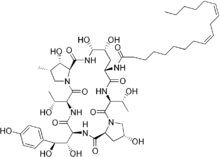

Chemistry

The present-day clinically used echinocandins are semisynthetic pneumocandins, which are chemically lipopeptide in nature, consisting of large cyclic hexapeptoids. Caspofungin, micafungin, and anidulafungin are similar cyclic hexapeptide antibiotics linked to long modified N-linked acyl fatty acid chains. The chains serve as anchors on the fungal cell membrane to facilitate antifungal activity.[9] Due to their limited oral bioavailability, echinocandins are administered through intravenous infusion.[10]